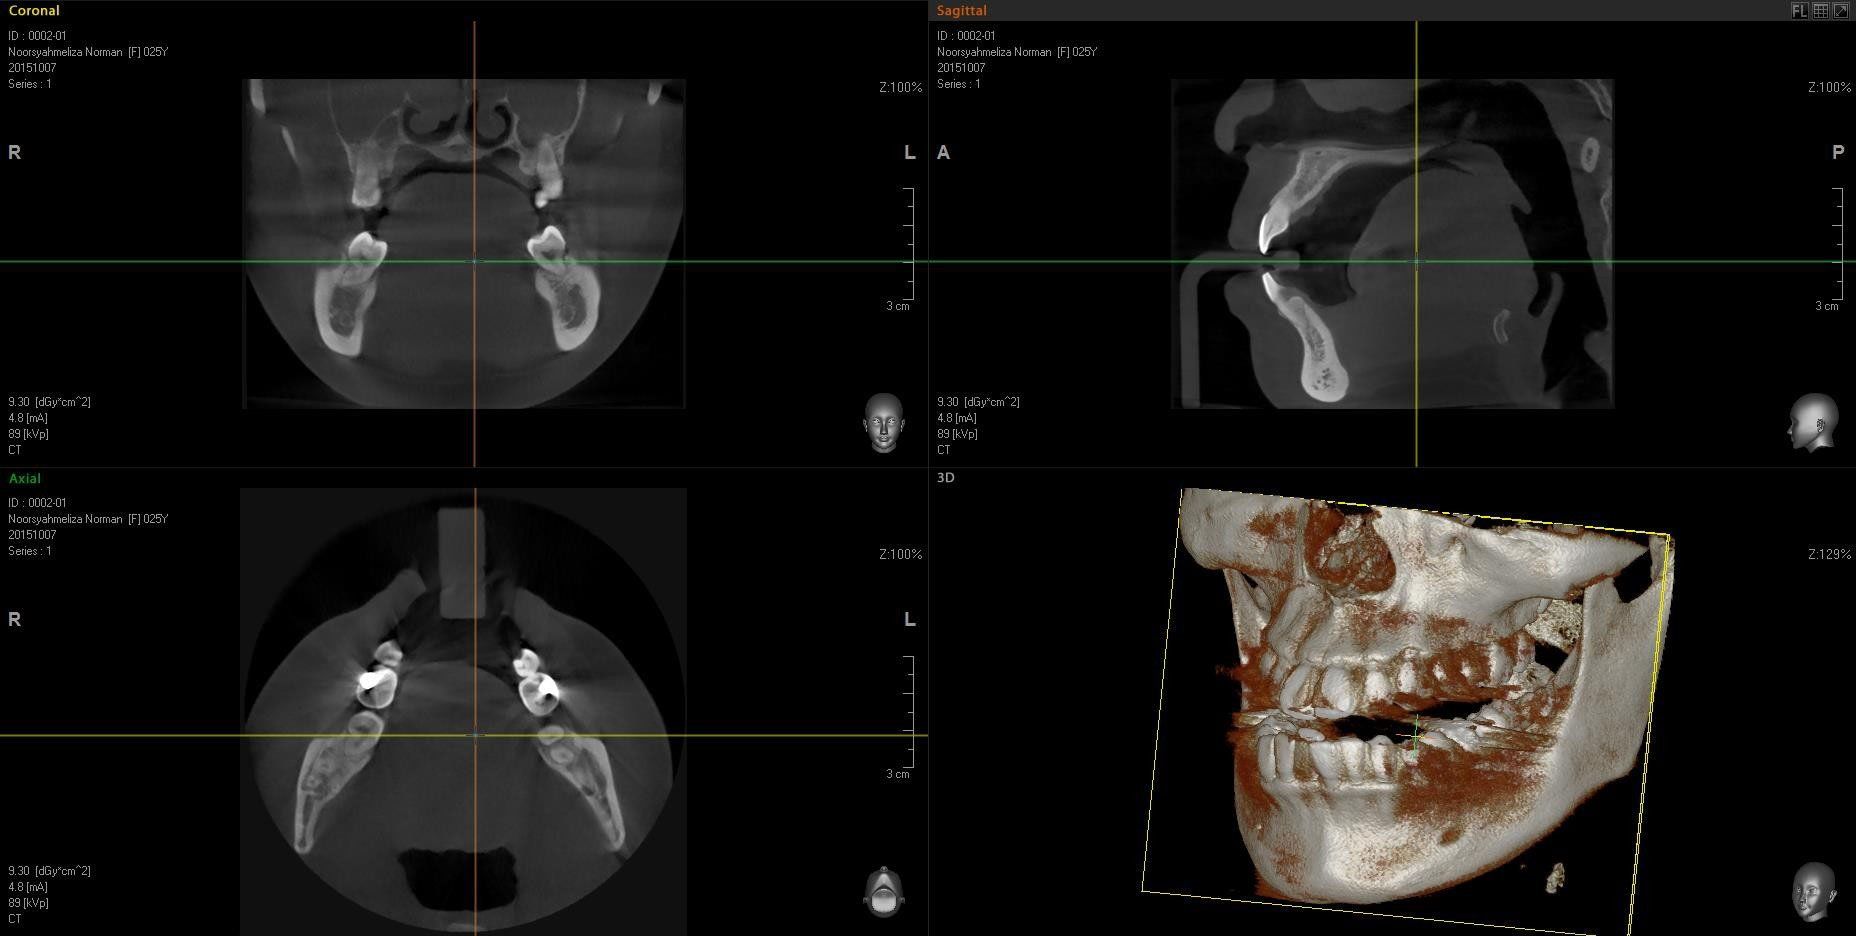

A Tomografia Computadorizada da Raio-X Mangabeiras possui a mais avançada técnica de aquisição volumétrica na odontologia e é uma importante ferramenta para o planejamento de procedimentos odontológicos, principalmente para o tratamentos com implantes, além de apresentar uma abordagem sistemática dos transtornos orais e das articulações da região da boca.